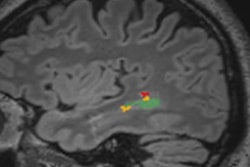

Relaxivity can be thought of as the potency of an MRI contrast agent, according to Kanal, who is director of MR services at the University of Pittsburgh Medical Center. A certain amount of relaxivity is required to prompt anatomical structures to enhance on MRI scans.

A new class of high-relaxivity agents is coming to market that has the potential to provide the same level of enhancement but with less contrast material. This could give radiology facilities the opportunity to use less MRI contrast than previously required, saving money and exposing patients to less contrast.